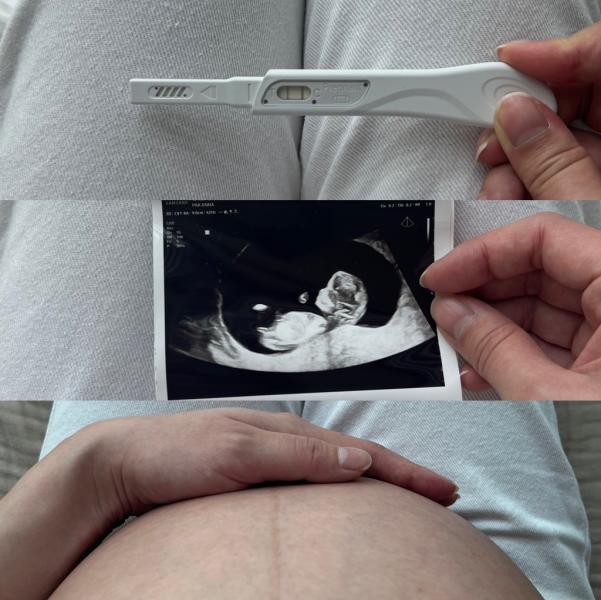

Но там были две полоски. Обрадовалась ли я им? Да. Но планов не строила. После 4 потерь полоски ничего не значат.

Были мучительные ожидания хгч. Который в это раз рос, как на дрожжах!) были мучительные ожидания УЗИ. Было много слез также. Сначала была двойня, потом один замер. Потом риски синдрома дауна. Потом ицн. Зашитие шейки, лежка 80% времени. Все это в другой стране, на чужом языке.